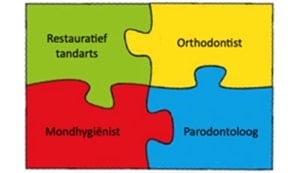

Parodontale chirurgie

Parodontale chirurgie moet worden uitgevoerd door bevoegde en bekwame professionals.

Stap 4: Nazorg

Stap 4 bestaat uit nazorg waarbij eerst de situatie wordt beoordeeld. Het is ook belangrijk dat de patiënt zelf zorgt voor supragingivale plaquecontrole door middel van het begeleiden van de patiënt met het gebruik van een elektrische tandenborstel en cilindrische ragers. Het bijsturen van de motivatie en instructie is een belangrijk onderdeel van de nazorgbehandeling. Uiteraard wordt er een professionele gebitsreiniging uitgevoerd, sub en supragingivaal. Bloeding na sonderen is daarvoor een belangrijke parameter. Uiteindelijk voor een nazorg behandeling afgerond met polijsten en op inidctaie het aanbrengen van fluoride. Ten slotte wordt een recall interval wordt bepaald tussen 3 en 12 maanden. Belangrijke factoren om dit interval te bepalen zijn roken, diabetes, aantal pockets > 5 mm, BOP% en hoeveelheid botverlies. Om deze stappen binnen de nazorg goed te kunnen doorlopen en voldoende tijd te kunnen besteden aan alle aspecten is het zo genoemde “profy hour” bedacht.

Complexe (parodontale) problematiek

Er is sprake van complexe parodontale problematiek wanneer parodontitis gecombineerd is met: